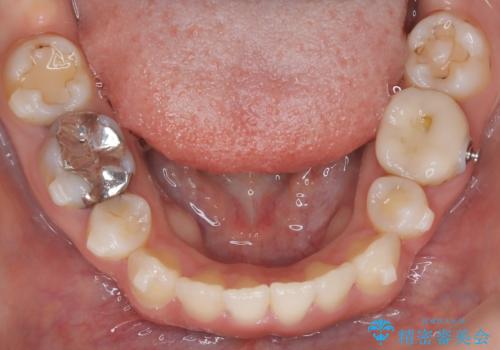

- 上下の歯の中心(正中)のズレと、口元の見た目を気にされて来院されました。精密な検査の結果、咬み合わせのバランスを整えながら、正中線を一致させる治療が必要と判断。患者様のご希望に合わせ、透明で目立ちにくいインビザライン(マウスピース矯正)による治療計画を立案しました。歯列全体を奥(遠心)へ移動させるためにゴムかけを併用。さらに、見た目を改善するため、既存の金属の被せ物をセラミッククラウンに交換することも治療計画に組み込みました。

今回の矯正治療では、透明なマウスピース型の装置インビザラインを使用しました。歯列を奥へ動かす遠心移動の効率を高めるため、患者様ご自身にゴムかけも行っていただきました。この併用によって、歯をより正確かつスムーズに動かすことができ、上下の歯の中心である正中線を一致させることが可能になりました。また、治療の最終段階では、以前から入っていた金属の被せ物を、天然歯に近い色合いのセラミッククラウンに交換。矯正治療と審美治療を組み合わせることで、機能的な咬み合わせの改善に加え、金属が見えない、より自然で美しい口元を獲得していただけました。